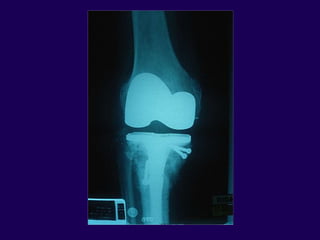

Complications in Total

Knee Arthroplasty

Periprosthetic Fractures

Infected Total Knee

Arthroplasty